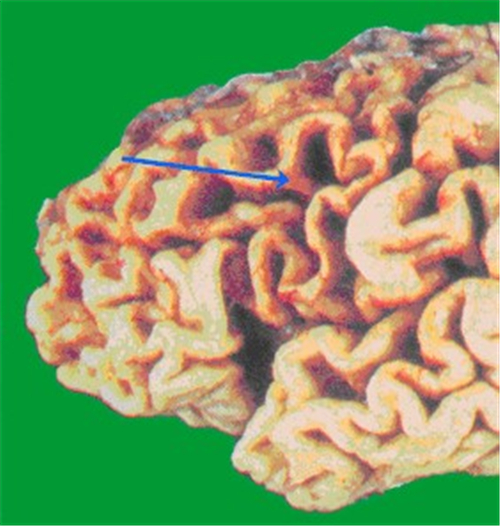

腦供血不足致腦萎縮